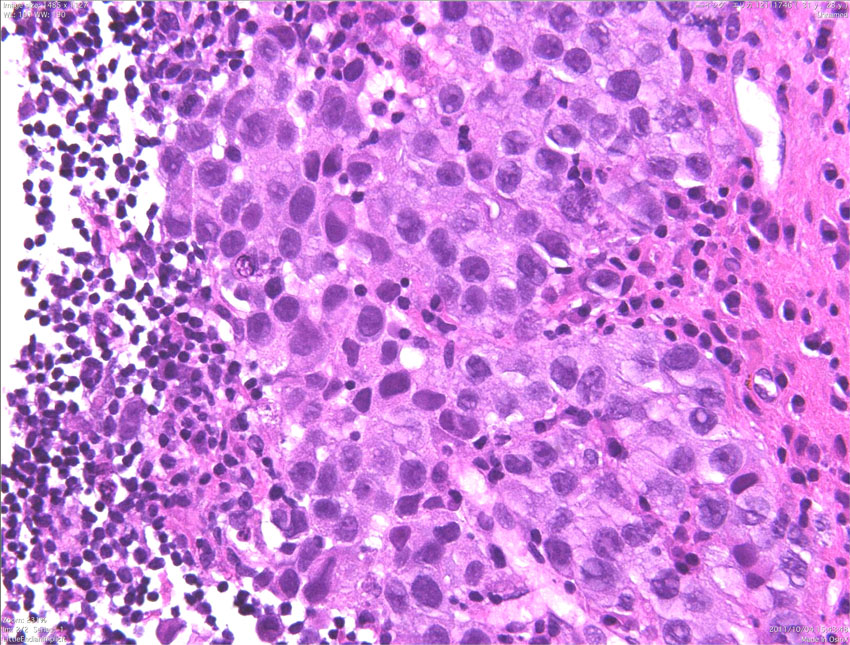

ジャーミノーマ(胚腫)の病理

(ここをクリックするともっとたくさん見えます)

病理診断は困難ではありません。左側の写真のように,多くの場合にHE染色でtwo-cell patternと呼ばれる, 大型の腫瘍細胞と小型のリンパ球浸潤の特徴的な病理像で診断がつきます。大型の腫瘍細胞は楕円形の大きな核に大きな核小体が特徴です。